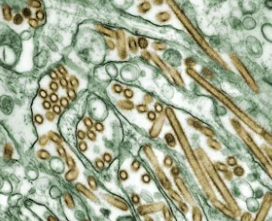

최근 중국 연구진이 저널 Cell에 발표한 논문을 통해 신종 박쥐 코로나 바이러스인 HKU5-CoV-2가 발견되면서, 전 세계적으로 큰 관심을 받고 있다. 이 바이러스는 코로나19를 유발하는 SARS-CoV-2와 동일한 인간 세포 표면 수용체인 ACE2를 사용하여 침투할 가능성이 있다는 연구 결과가 발표되었으며, 이에 따른 투자심리 변화와 함께 국내 코로나 테마주가 강세를 보이고 있다. 본 포스트에서는 신종 박쥐 코로나 바이러스의 연구 배경, 전파 가능성, 그리고 주식 시장 반응에 대해 자세히 분석해보고자 한다.

지난 2월 24일, 중국 연구진은 박쥐 샘플에서 새로운 코로나 바이러스 HKU5-CoV-2를 분리해냈다. 이 바이러스는 기존 코로나19 바이러스와 유사한 세포 침투 메커니즘을 가지고 있어, 동물에서 사람으로 전파될 가능성이 제기되었다. 연구진은 “HKU5-CoV-2는 인간의 ACE2 수용체에 잘 적응하며, 기존 코로나 바이러스보다 더 넓은 숙주 범위와 높은 종간 감염 잠재력을 지닐 수 있다”고 설명하였으나, 동시에 “바이러스가 실제로 인간에게 전파될 가능성은 추가 조사가 필요하다”고 덧붙였다.

연구 결과에 따르면, HKU5-CoV-2는 인간의 ACE2 수용체와 결합하는 특성을 보이며, 기존의 코로나바이러스보다 감염력이 더 강할 가능성이 제시되고 있다. 그러나 연구진은 “실제 인체에서 전파될 수 있는지는 아직 명확하지 않다”며, 추가 연구와 검증이 필요함을 강조하고 있다.